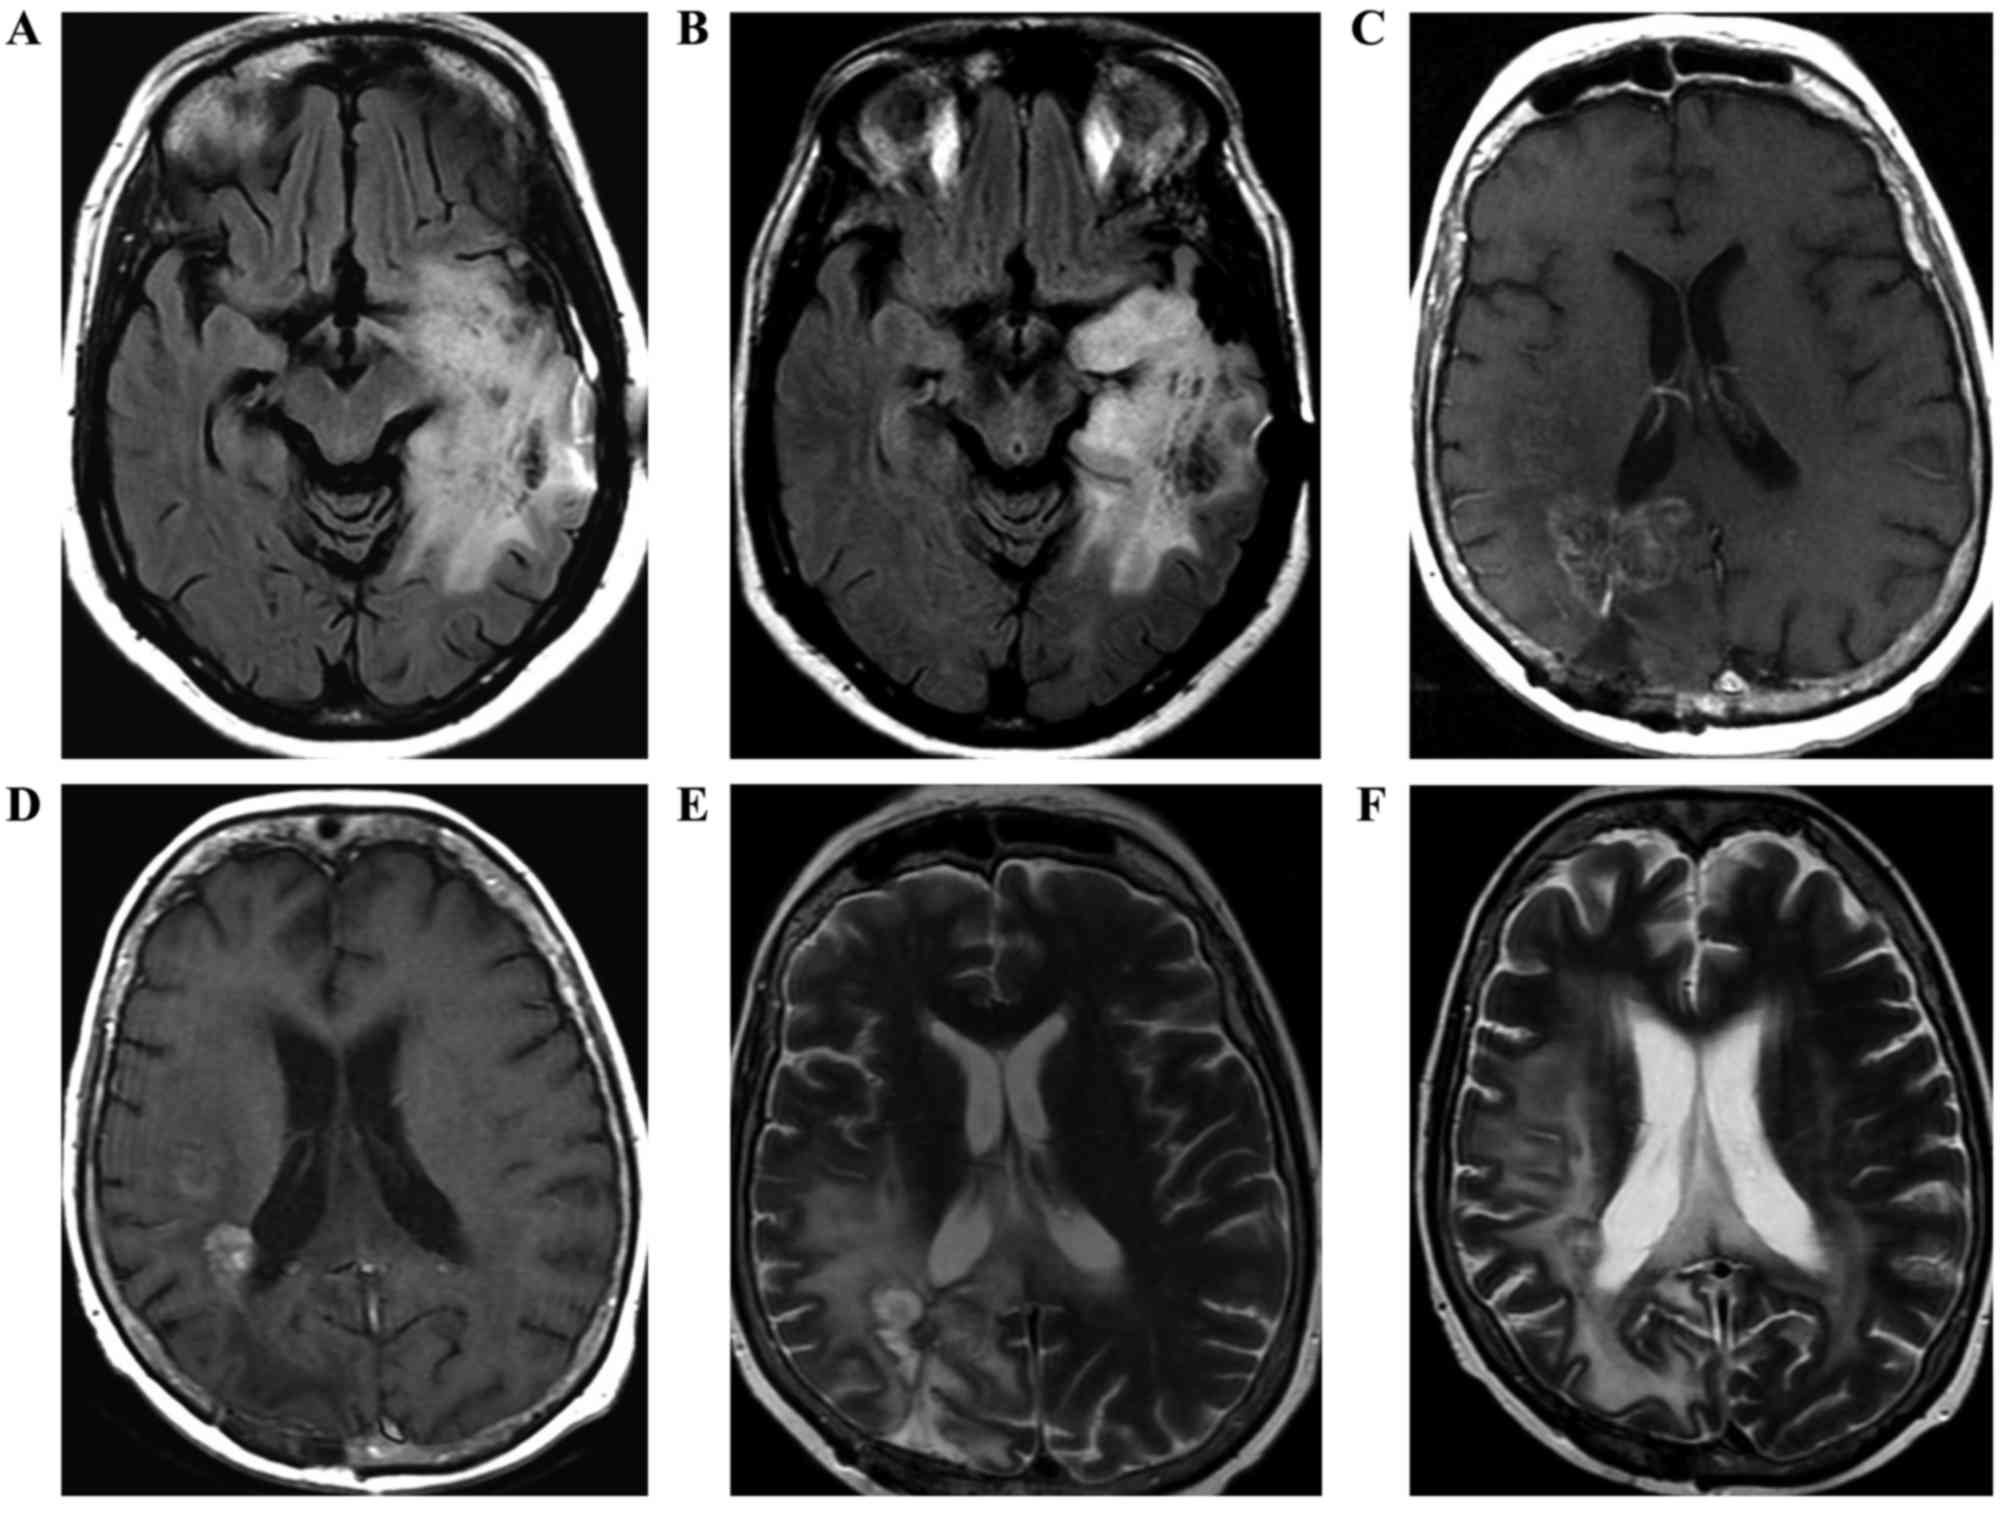

Following three months of adherence to the treatment in the KD group, PR was observed in 77.8% (7/9) patients, characterized by the reduction of MRI tumor size and peritumoral edema (Fig. 1), neurological stability, reduced corticosteroid requirement, and the general improvement of condition. The corticosteroid was maintained during the trial for all patients, but the dose was decreased in the patients who presented with an improvement of clinical status (5/9 patients). PD was observed in 11.1% (1/9) patients, with an increased tumor size or the appearance of a new lesion in MRI. Among the patients of the control group, PR was noted in 25.0% (2/8 patients), and PD was observed in 50.0% (4/8 patients). The imaging data demonstrated that tumor area was significantly smaller in the KD group at 90 days compared with the baseline (P=0.035), and not in the control group (P=0.687; Fig. 2).

Figure 1.

Brain magnetic resonance images of three patients, with images prior to (A,C,E) and following (B,D,F) the commencement of treatment. (A) Axial flair shows part of the expansive lesion and the extensive perilesional edema in the left temporoparietal region, which extends along the left cerebral peduncle. (B) Axial flair in the control shows reduction of lesion dimension. (C) Axial T1W contrast-enhanced image demonstrates lesion with peripheral and irregular enhancement and perilesional edema. (D) Axial T1W contrast-enhanced image of the control with reduction of tumor volume following therapy. Postoperative changes in correspondence. (E) Axial flair demonstrates a heterogeneous lesion with hyperintense area. (F) Axial flair of the control shows reduction in the dimensions of the heterogeneous lesion with extensive perilesional edema. Magnetic susceptibility artefact by previous biopsy.

In our previous study, it was demonstrated that although the consistent use of intranasal POH in recurrent GBM patients induced clinical responses, MRI data presented no evidence for the regression in the extent of peritumoral edema (42). In the present study, the extent of peritumoral edema was notably reduced, along with a decrease of the tumor area (Figs. 1 and 2). These results are consistent with another study (43) that investigated the effects of the KD on tumor growth and progression in animal models. The results revealed that peritumoral edema was significantly reduced in animals fed the KD, and protein analyses showed altered expression of zona occludens-1 and aquaporin-4. The authors concluded that the KD directly or indirectly altered the expression of several proteins involved in malignant progression and may be a useful tool for the treatment of gliomas. In addition to the MRI-based observation of decreased cerebral edema and tumor volume, a significant decrease in cholesterol and cholesterol esters in particles of LDL was identified in the present study. This observation is in line with an earlier study that demonstrated that proliferating tumor cells utilize serum-derived cholesterol esters, which are presumably carried by LDL particles (44). The decrease of cholesterol in the present study can be explained as there was attention to the quality of the lipids offered (monounsaturated fatty acid > polyunsaturated > saturated fatty acid) and the amount of cholesterol was limited to 200 mg/day. These results are not consistent with other studies (44–46), which concluded that KD increased the serum levels of total lipids and LDL-C. However, Sharma et al (47) did not observe significant alterations to the lipid profile of children with refractory epilepsy treated with KD, which remained within normal limits throughout the study.